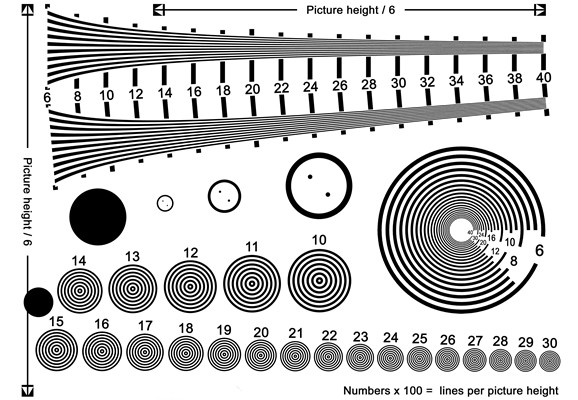

散光圖片

散光度數測試圖 (48)

散光度數測試圖 (49)

散光度數測試圖 (5)

散光度數測試圖 (50)

散光度數測試圖 (51)

散光度數測試圖 (6)

散光度數測試圖 (7)

散光度數測試圖 (8)

散光度數測試圖 (9)

散光度數測試圖 (39)

散光度數測試圖 (4)

散光度數測試圖 (40)

散光度數測試圖 (41)

散光度數測試圖 (42)

散光度數測試圖 (44)

散光度數測試圖 (45)

散光度數測試圖 (46)

散光度數測試圖 (47)

散光度數測試圖 (35)